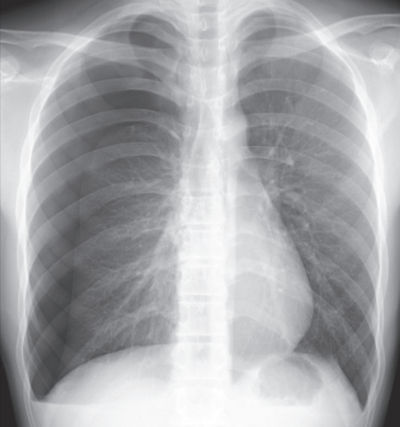

検査所見:血液所見:赤血球 480万、Hb 15.0 g/dL、Ht 45%、白血球 7,800、血小板 26万。血液生化学所見:AST 32 U/L、ALT 36 U/L、LD 280 U/L(基準 120~245)。来院時の胸部エックス線写真を別に示す。

来院時